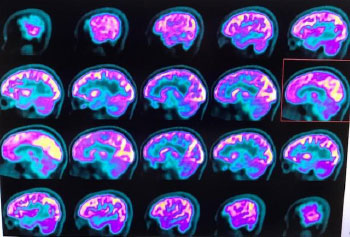

The patient’s brain computed tomography (CT) and magnetic resonance imaging scans showed no abnormalities. Blood laboratory tests were also requested and did not reveal any signs of infectious and inflammatory activity. A neurological positron emission tomography (PET)/CT scan was requested which, after intravenous injection of a radiopharmaceutical tracer (18fluorodeoxyglucose, 18FDG-PET), showed a mild reduction in glucose metabolism in the bilateral mesial frontal region, slightly more evident on the right, as well as in the bilateral frontobasal region (bilateral gyrus rectus and anterior cingulate gyrus). The concentrations of the radiopharmaceutical were preserved in the other cortical regions of the cerebral and cerebellar hemispheres, basal ganglia, and thalamus (Figs. 1 and 2).

In contrast, we do not have a valid explanation for the cortical dysfunction that leads to cerebral hypometabolism and the clinical signs observed. Similar to septic encephalopathy after bacterial infections, a systemic immune response triggering an inflammatory reaction within the brain that can disrupt the blood-brain barrier, impair astrocyte clearance at synapses, and disturb microcirculation, may be suggested [15]. In the present case, cortical hypometabolism may be the remnant of an inflammatory process triggered by a systemic immune response. The fact that SARS-CoV-2 is able to replicate in neuronal cells and infect human brain organoids highlights the neurotropism of this viral agent.

Other mechanisms of action must have been responsible for the signs and symptoms of our patient that occurred during her healthy phase of adolescence. A possible explanation could be given, as in other studies, with our result obtained by the images evidenced in the neurological PET/CT, as submitted by the patient [6, 14, 15, 20].